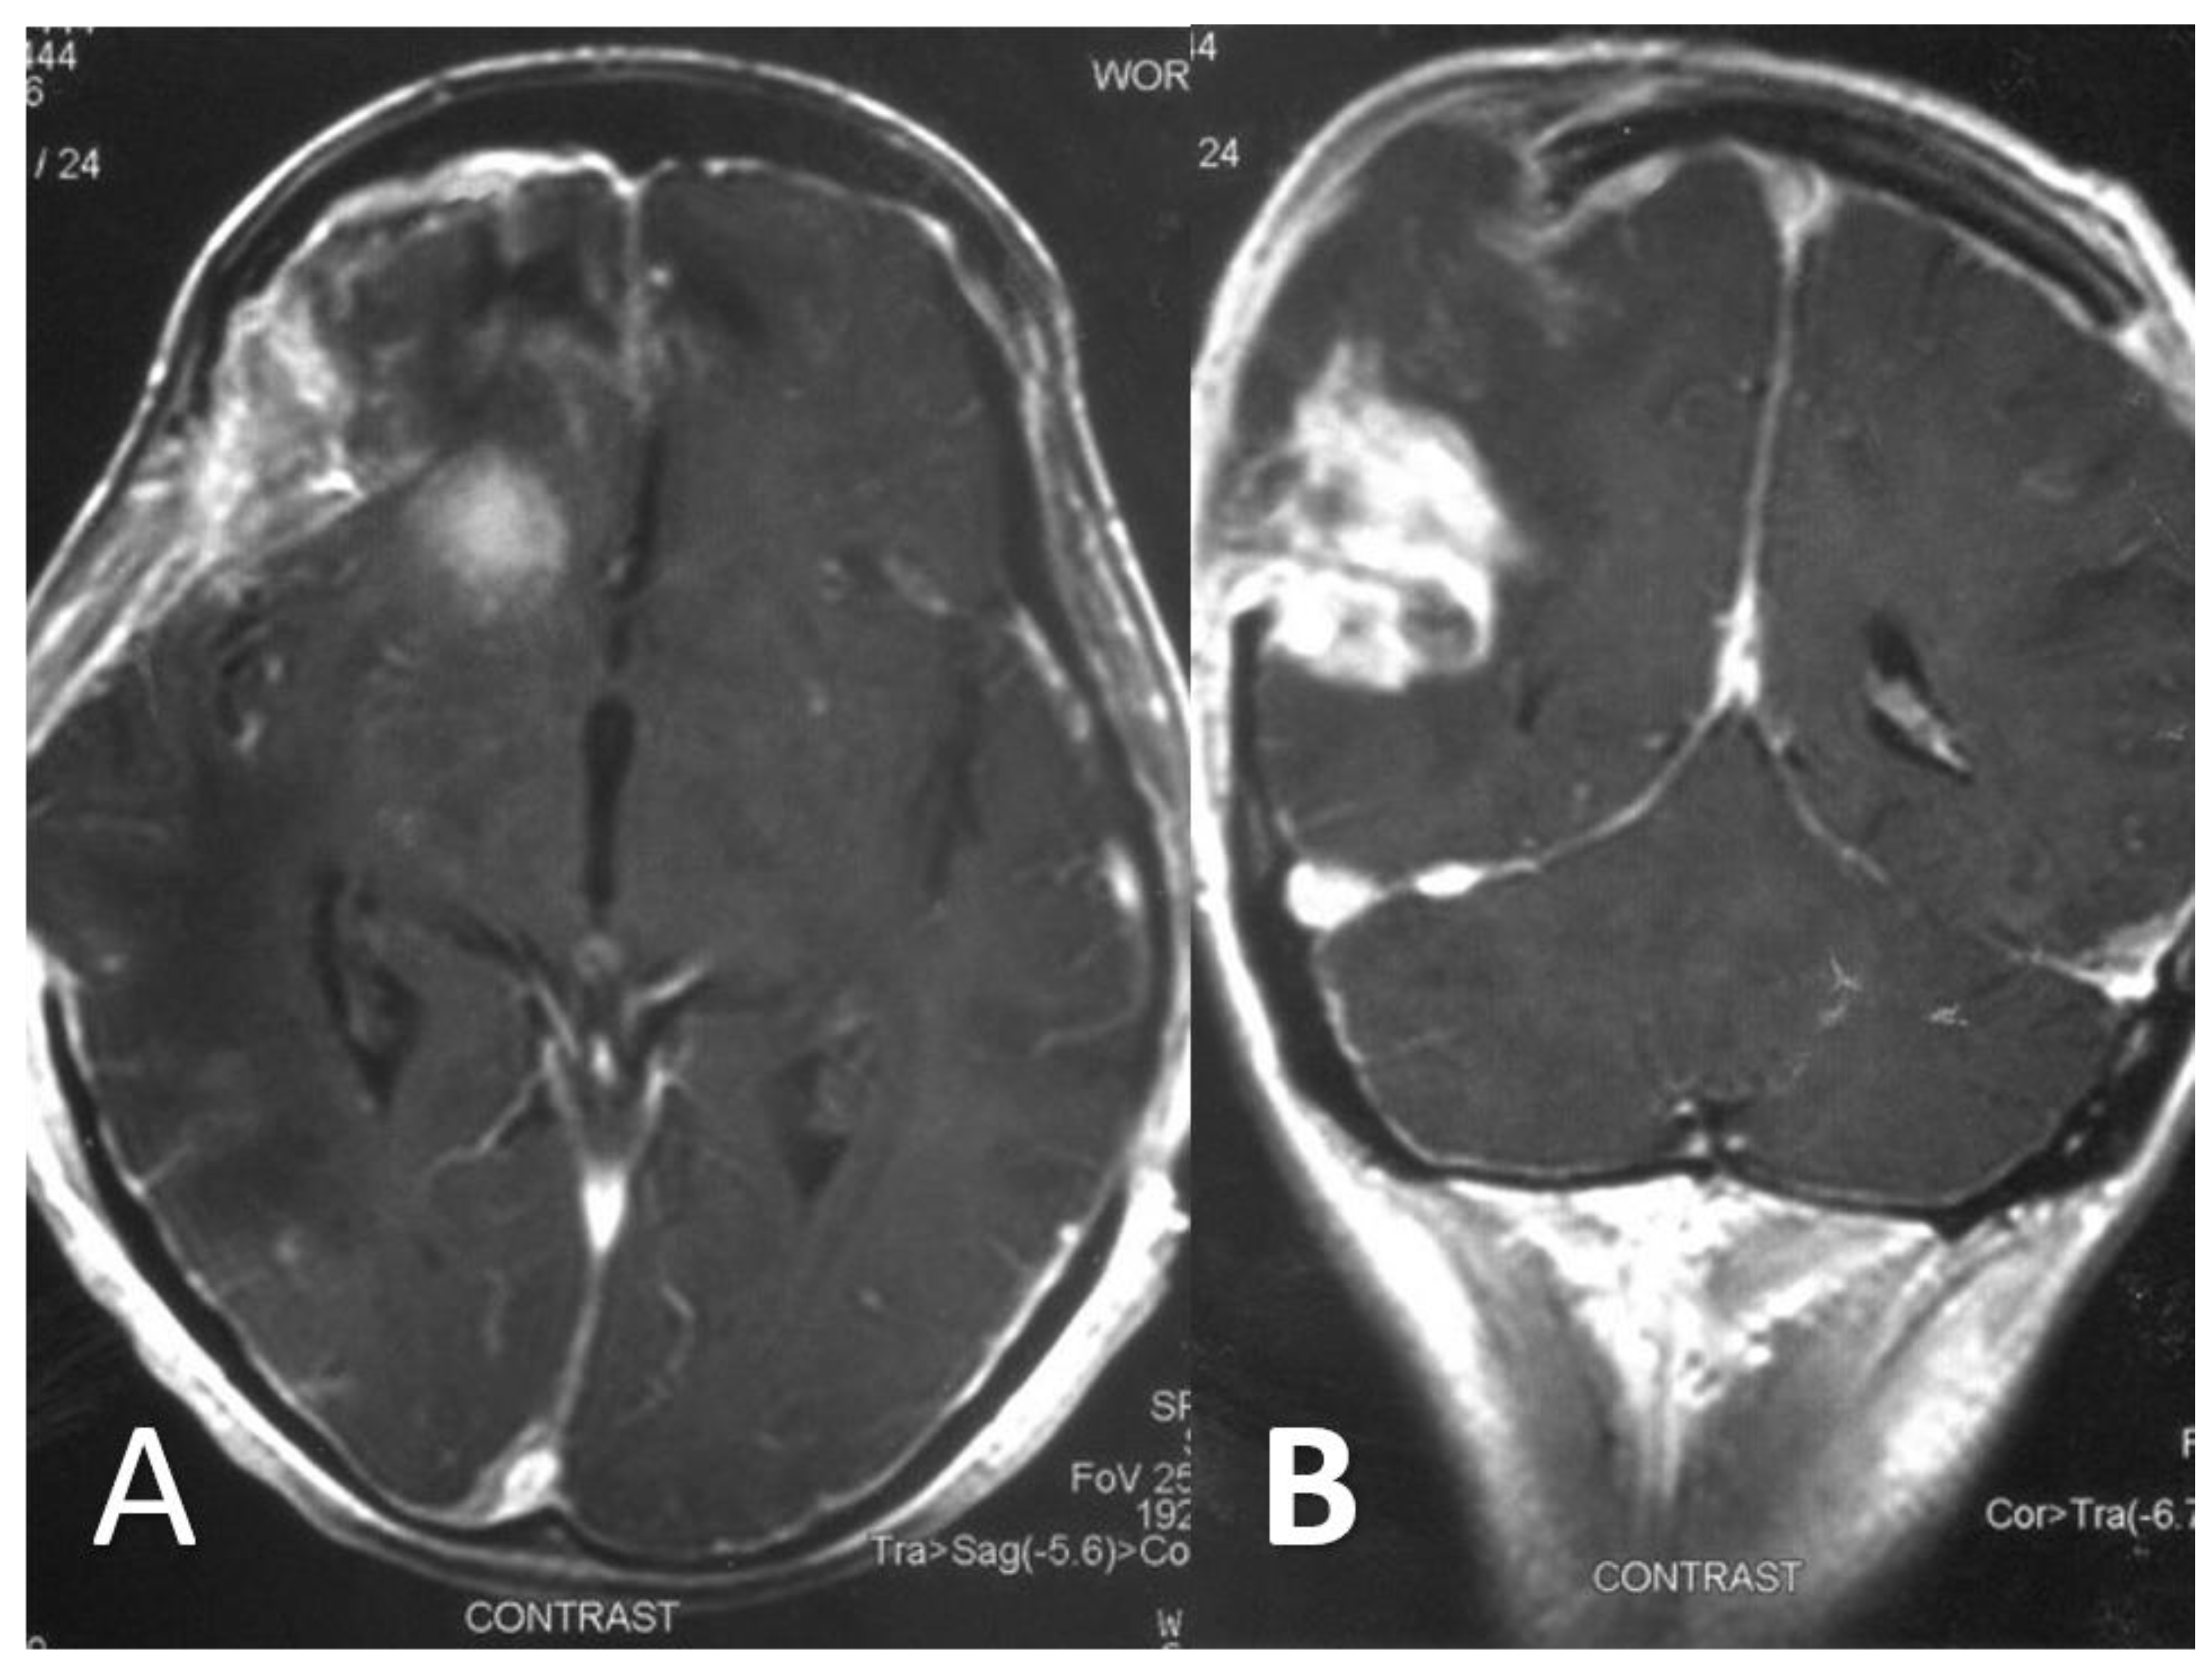

At that point, a new CT scan revealed parietal, temporal and frontal abscesses at the right side (Figure 2). The patient underwent surgery; surgical debridement was performed, while specimens were microscopically and histologically examined, as well as cultured. Direct microscopy with fluorescent dye (Blankophor P) again revealed the same findings, compatible with mucormycosis. Furthermore, hematoxylin–eosin stain, performed in tissue specimens, showed fungal elements similar to those with BlanKophor P (Figure 3). It is of note that cultures did not yield any fungal organism at this point, probably due to the treatment with liposomal amphotericin B. Magnetic resonance imaging (MRI) performed postoperatively, for the evaluation of the infection’s course, revealed enclosed collections absorbing contrast, indicating abscesses at the parietal, temporal and frontal lobe at the right side (Figure 4).

Regarding imaging techniques indicating diagnosis, the modality of choice is brain MRI with special sequences, including gradient echo and susceptibility weighting, to assess for microhemorrhage, indicating a potentially invasive process [16]. However, as shown in the reported case, contrast CT scanning may also be useful during the diagnostic process, revealing infectious regions [4,20].

Figure 4. Axial (A) and coronal (B) T1 gadolinium-enhanced MR images following partial surgical debridement showcase a contrast-enhancing round lesion in the right anterior cranial fossa (A), and a heterogeneously enhancing lesion in the right parietal lobe (B). Additionally, markedly increased meningeal enhancement is also depicted in the right cerebral hemisphere (A), suggesting concomitant meningoencephalitis.